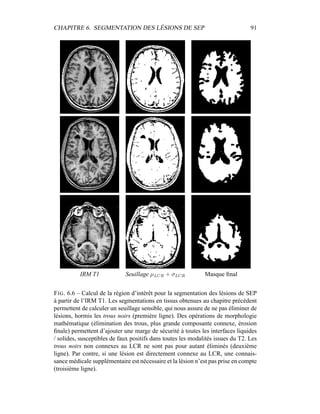

troscopie par résonance magnétique (Magnetic Resonance Spectroscopy, MRS),

tomographie par émission de positons (Positron Emission Tomography, PET), to-

mographie par émission monophotonique (Single Proton Emission Computerized

Tomography, SPECT), ou IRM avec produit de contraste. Les biomarqueurs molé-

culaires sont enfin acquis de manière similaire aux marqueurs fonctionnels, mais

donnent des mesures précises sur un composant spécifique à l’aide des imageries

PET ou SPECT.

En général et particulièrement dans le cadre d’études sur la sclérose en plaques,

les biomarqueurs issus de l’imagerie sont particulièrement utiles dans la phase II